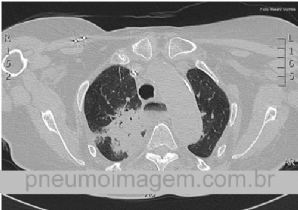

CASO CLÍNICO #10

Paciente do sexo masculino, 60 anos, com histórico de quadro gripal há 4 dias associado à febre. Há um dia com dispneia, tosse produtiva, deu entrada no Serviço de Emergência em insuficiência respiratória e importante dessaturação. Nega antecedentes pulmonares...